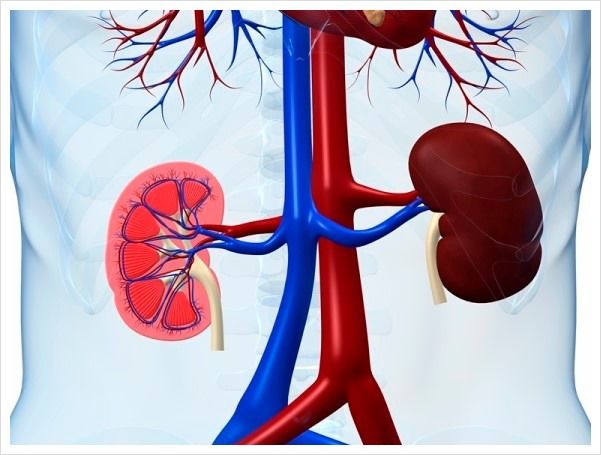

신장 낭종은 콩팥 안이나 표면에 물이 고여 주머니처럼 형성된 것을 말합니다. 말 그대로 신장 내부에 액체가 차 있는 주머니가 하나 또는 여러 개 생긴 상태입니다. 신장 낭종은 대부분 얇은 막으로 둘러싸여 있고, 내부에는 맑은 액체가 들어 있습니다.

일반적으로 나이가 들수록 생길 가능성이 높으며, 특히 50세 이후에는 비교적 흔하게 발견됩니다. 대부분의 경우 특별한 증상을 일으키지 않고 건강검진이나 초음파 검사 중 우연히 발견되는 경우가 많습니다. 하지만 낭종의 크기가 커지거나 여러 개가 생기면 주변 조직을 눌러 불편감을 유발할 수 있습니다.